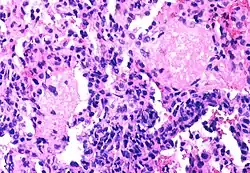

The spectrum of AIDS-related infections seen in different populations proves that AIDS is actually many diseases not caused by HIV

The diseases associated with AIDS, such as Pneumocystis jiroveci pneumonia (PCP) and Mycobacterium avium complex (MAC), are not caused by HIV, but rather result from the immunosuppression caused by HIV disease. As the immune system of an HIV-infected individual weakens, he or she becomes susceptible to the particular viral, fungal, and bacterial infections common in the community. For example, HIV-infected people in the Midwestern United States are much more likely than people in New York City to develop histoplasmosis, which is caused by a fungus. A person in Africa is exposed to pathogens different from individuals in an American city. Children may be exposed to different infectious agents compared to adults.[87]

HIV is the underlying cause of the condition named AIDS, but the additional conditions that may affect an AIDS patient are dependent upon the endemic pathogens to which the patient may be exposed.